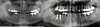

POSE DE DEUX COURONNES CÉRAMIQUES SUR IMPLANTS MOLAIRES MANDIBULAIRES